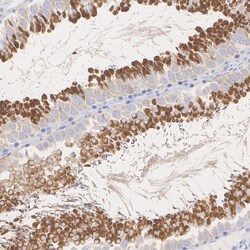

Positive Control: K-562 cell lysate, Jurkat cell lysate, HEK-293 cell lysate, COS-1 cell lysate, Mouse brain tissue lysate, Mouse testis tissue lysate, Rat testis tissue lysate, human testis tissue, mouse testis tissue, rat testis tissue.Tissue Specificity: Low tissue specificitySubcellular Location: Nucleus, Cytoplasm, Membrane, Mitochondrion.Sequence Similarities: 92% Mouse/RatPredicted band size: 49 kDa.

| Immunohistochemistry (Paraffin), Immunoprecipitation, Western Blot | |